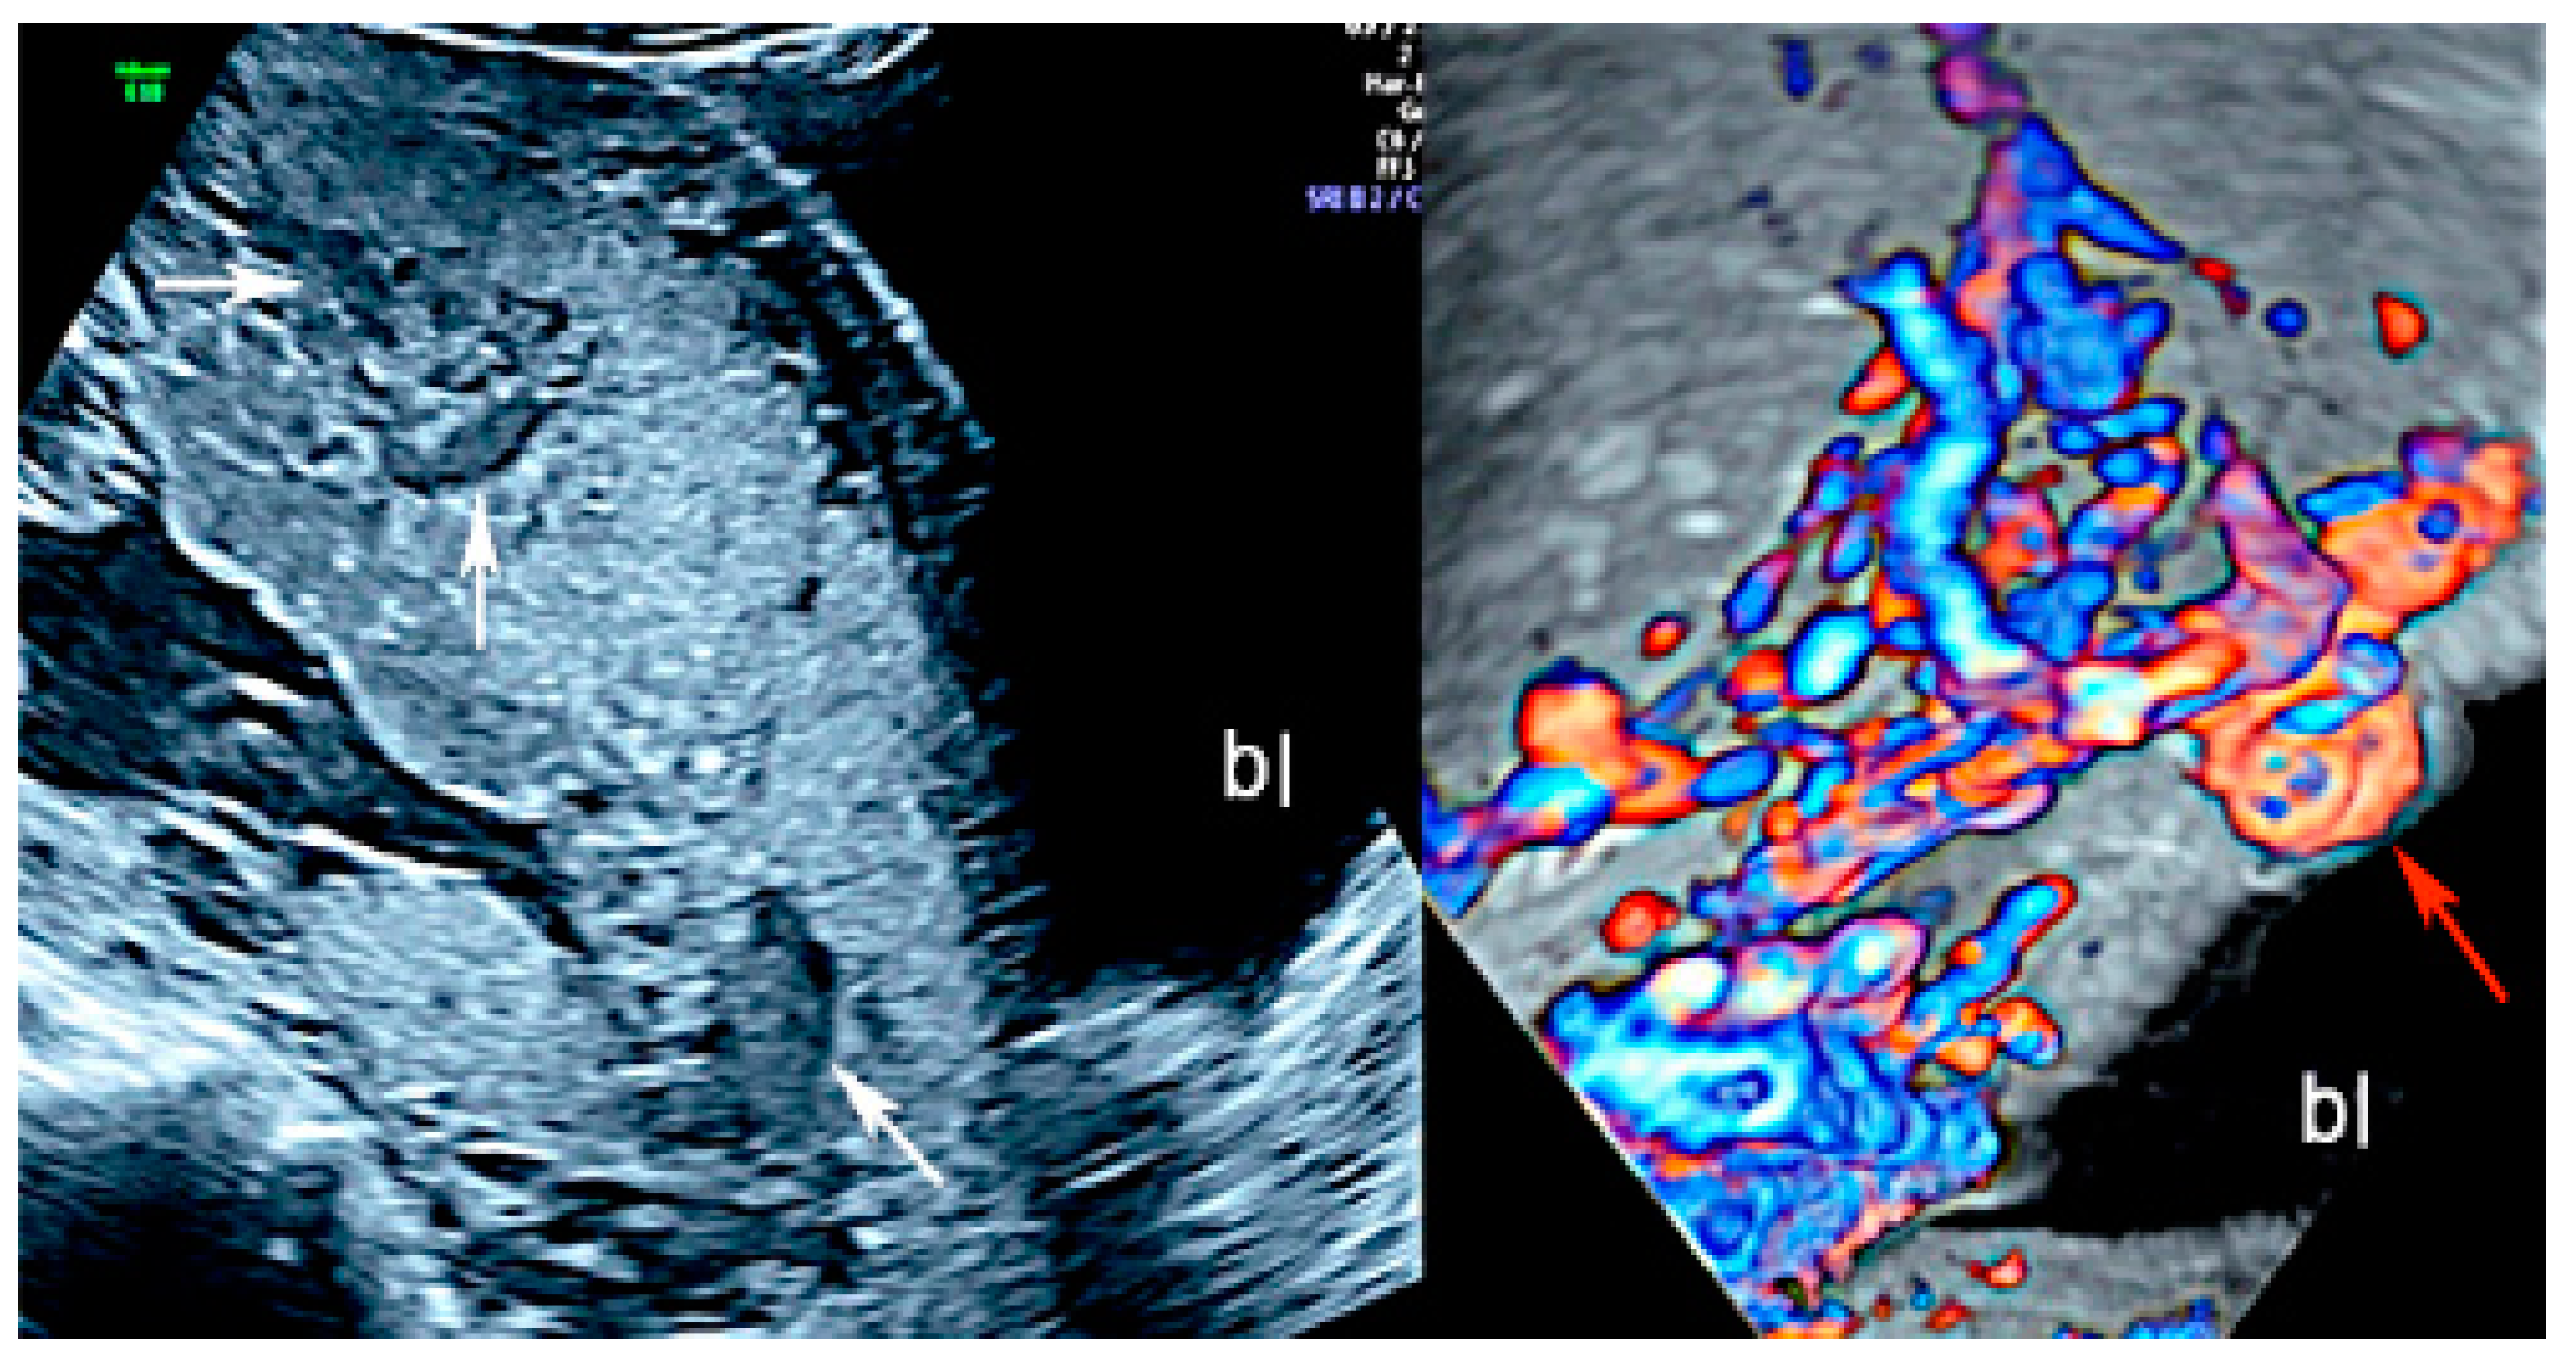

Placenta accreta spectrum (PAS) is the general term used to describe abnormalities related to the adherence of the placental trophoblast to the uterine endometrium and myometrium [6,7,8,9,10]. The PAS includes three types of anomalies: placenta accreta, which is the excessively firm attachment of the placenta to the endometrium decidua; placenta increta, which is characterized by the invasion of the trophoblast into the myometrium; and placenta percreta, in which the myometrium, serosa and even surrounding structures are invaded by placental peptides [6,7,8,9,10]. Adherent placenta is histologically caused by the trophoblast’s invasion of the spongiosa layer of the decidua, possibly because of a damaged or deficient Nitabuch’s layer [7,8,10], and its incidence has risen due to the increase of surgical procedures, such as myomectomy, Cesarean section, endometrial ablation and uterine curettage [6,7,8,9]. PAS may be associated with an increase in maternal mortality, mainly due to massive bleeding and its consequences after attempting to separate the placenta from the myometrium but also after uterine rupture [6,11]. Several studies have documented that ultrasonography performed by an experienced operator has the sensitivity and specificity in the grey scale modality as high as 90%, and sonographic markers associated with PAS are multiple vascular lacunae, the loss of the normal hypoechoic retroplacental zone in the myometrium, the abnormality of the uterine serosa-bladder interface, the thinning of the retroplacental myometrium, the bulging of the lower uterine segment, and increased placental vascularity on color Doppler [6,9,10,11,12,13,14,15]. (Figure 1).

Figure 1.

Two-dimensional ultrasound imaging showing PAS (placenta accreta spectrum, placenta increta type): longitudinal scan in a patient at 24 week’s gestation shows multiple hypoechoic areas (lacunae) (white arrows). Color Doppler ultrasound shows increased vascularity and the bulging of the placenta increta (red arrow); (bl): bladder.